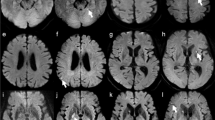

Table 2 lists the image quality scores of readers 1 and 2 for each sequence. The kappa values of inter-rater agreement for geometric distortion, susceptibility artifacts, overall image quality, and anatomic visualization of trigeminal nerve and vestibulocochlear nerve were 0.98, 0.98, 0.89, 0.74 and 0.60, respectively, showing good or very good agreement. The scores for geometric distortion, susceptibility artifacts, and overall image quality were the best for both readers in TGSE-BLADE DWI (P < 0.001), and better in RESOLVE DWI than in SS-EPI (P < 0.001). The scores for anatomic visualization of the two cranial nerves were better for both readers in TGSE-BLADE DWI than in the other two DWI sequences (P < 0.001). There was no significant difference between RESOLVE DWI and SS-EPI DWI for the two cranial nerves in reader 1, and no significant difference only for trigeminal nerve in reader 2. Representative images of the three DWIs are shown in Fig. 2.

Representative images of SS-EPI DWI (a, d, g), RESOLVE DWI (b, e, h), and TGSE-BLADE DWI (c, f, i) in a 67-year-old healthy female volunteer. The arrows indicate susceptibility artifacts. Artifacts are seen near air–bone interfaces in RESOLVE DWI and SS-EPI DWI, whereas few artifacts are seen in TGSE-BLADE DWI. The trigeminal nerve (arrowhead) in visualized in TGSE-BLADE DWI (f) but is blurred in RESOLVE DWI and SS-EPI DWI. The vestibulocochlear nerve (arrowheads in g–i) are best visualized in TGSE-BLADE DWI.